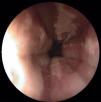

Los estudios de laboratorio fueron anodinos salvo una proteína C reactiva de 1,4mg/dl. Se realizó una endoscopia digestiva alta con toma de biopsias, que mostraba una mucosa esofágica en tercio inferior y medio intensamente inflamada con erosiones y úlceras longitudinales (fig. 1), siendo la mucosa del tercio superior normal.